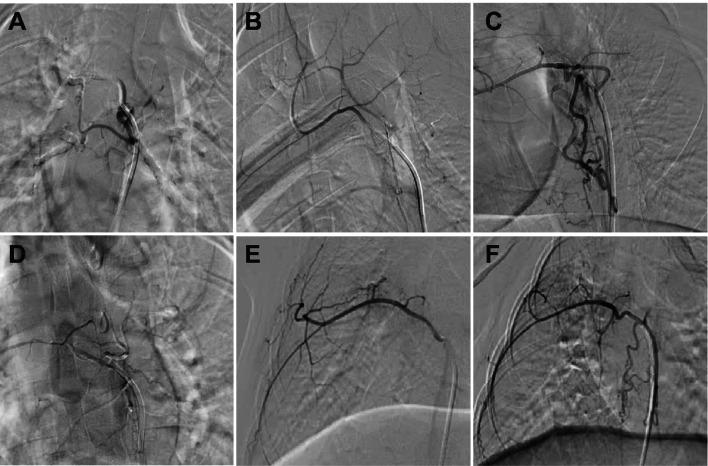

In preclinical evaluations, male beagles (n = 3/group) were randomized to receive 5 mg/kg aPD-1 mAb via BAI or intravenous routes (Venous group). Safety assessments included longitudinal imaging, biochemical analyses, and histopathological evaluation. Clinically, patients with advanced NSCLC meeting stringent inclusion criteria underwent BAI immunotherapy, with systematic monitoring of adverse events (AEs).

Both administration routes demonstrated comparable safety in canines, with no evidence of immune-related pneumonitis or structural lung alterations on CT or histology. Transient AEs (e.g., hematoma, lameness) resolved spontaneously. Pharmacokinetic analysis revealed similar systemic drug concentrations and tissue distribution between BAI and Venous groups (all p > 0.05). Biochemical profiling identified isolated mild LDH elevation in one BAI-treated canine. Notably, the BAI group exhibited significantly enhanced systemic IL-2 levels (80.15 ± 5.24 pg/mL vs. 66.47 ± 5.24 pg/mL in Venous groups, p = 0.001) at day 28, paralleled by elevated pulmonary IL-2 expression (626.90 ± 18.49 vs. 559.18 ± 45.61 pg/mg, p = 0.03). In the clinical cohort (n = 17; 94.1% male, mean age 61.6 ± 7.1 years), BAI immunotherapy was well-tolerated with mild AEs including nausea (n = 1), dyspnea (n = 1), atrial fibrillation (n = 1), and puncture-site hematoma (n = 1). No severe immune-related toxicities (e.g., pneumonitis) emerged during follow-up.